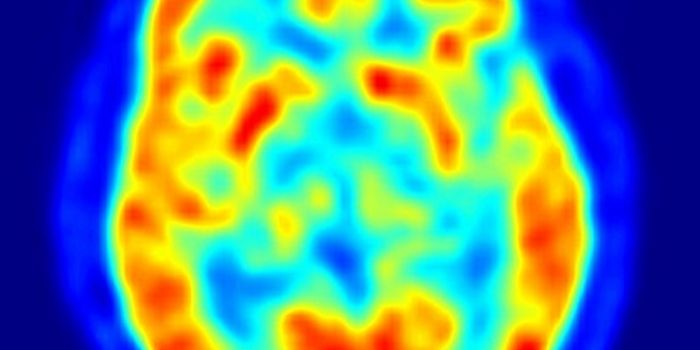

MAY 29, 2015NeuroscienceOne of the bigger questions in the field of neuroscience has been whether the amnesia that results from Alzheimer's or t ...

NOV 02, 2021Cell & Molecular BiologyDementia is an umbrella term for several age-related disorders that can cause cognitive problems such as dysfunction in ...